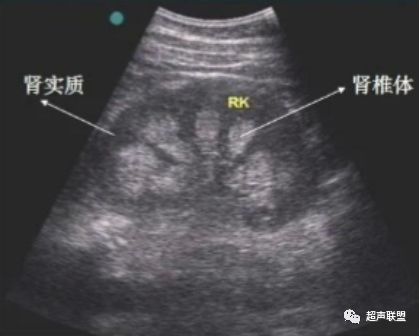

经典73 髓质海绵肾 超声联盟 微信公众号文章阅读 Wemp

腎臟 超 音波. 腎臟 超音波可以測量腎臟的大小腎實質的厚度腎實質就是長得像豌豆的腎臟的外圍部分包含腎絲球腎小管及腎間質等組織還有表皮的動脈血管等 如果腎臟變小腎實質變薄可能有腎功能變差腎盂腎炎的可能也可以檢查出 腎結石. 超錵 超バラニウム 在無重力空間下以錵和稀有金屬合成製造的新型合金硬度與熔點是錵的數倍以上蓮太郎的義肢皆是用此合金所製作似乎可以解決階段V黃道帶的原腸動物 造價非常的高昂以蓮太郎的義肢和義眼來說就至少有100億日元. Services for this domain name have been disabled.

肾脏超声波检查有什么临床意义 免疫相关肾脏健康科普96 资讯咖